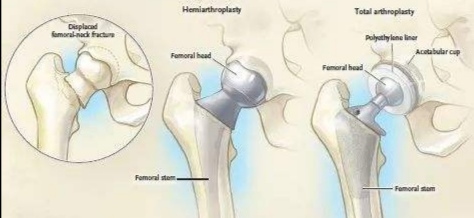

这种情况其实非常多见,比如说病人七八十岁,比如说病人还有高血压,糖尿病。那么这时候家属就要去评估了,如果你们认为他的预期寿命在15年以内,那么可以不选择全髋关节置换,而仅仅做人工股骨头置换,也叫做半髋置换,就是仅仅股骨头替换掉,而和股骨头相对应的髋臼部分不置换。如下图

最左边是股骨颈骨折示意图,中间是人工股骨头置换,右边是人工全髋关节置换。